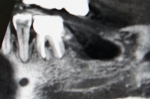

前歯部インプラント骨移植同時症例

大学病院よりご依頼いただいた症例。仮歯が入っていますが、欠損部歯茎が大きくへこんでいて、CT画像ではパノラマレントゲンで想定していたよりもかなり大きく骨がなかったですが、インプラント手術と骨の移植を同時に行い審美的にも回復しました。また同時に行うことにより治療期間が9か月→4か月の短縮されました。被せ物には審美性を考慮して土台からセラミックを使用しました。